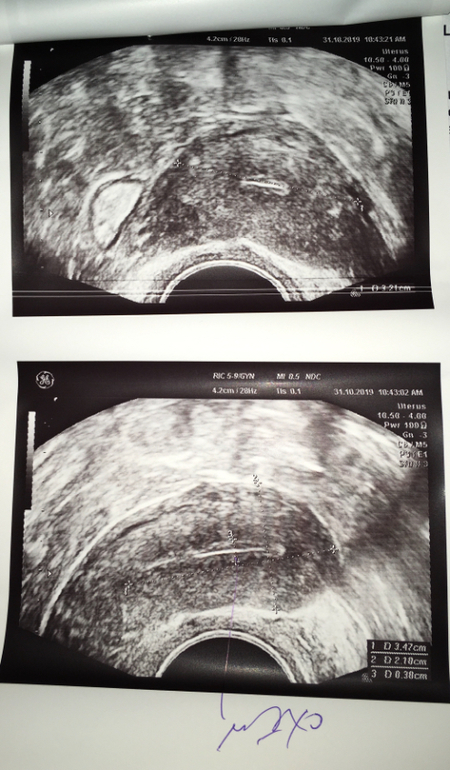

Сегодня была на узи - 10 ДЦ. Если вкратце : 2 фолликула в ЛЯ по 14 мм, эндометрий 3,8мм(( Кому интересно подробнее фотки прилагаю.